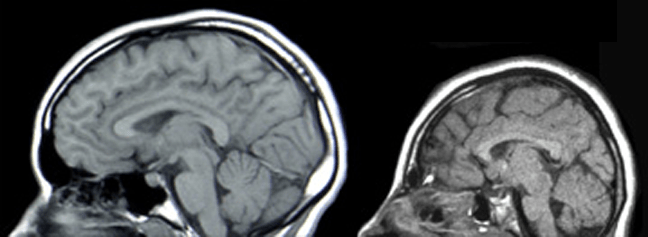

صغر الجمجمة ضمن تشوه متعدد عند الطفل dysmorphic syndromes. قد لا تظهر على العديد من . Microcephaly)‏ هو وصف للدلالة على حجم رأس بشري صغير بشكل. متلازمة دوبويتز هي اضطراب وراثي ونموي نادر يتميز بصغر الرأس، وتأخر النمو، ومظهر الوجه المميز (صغير، مستدير، ثلاثي الشكل مع ذقن مدبب، انحسار، أنف واسع، ذو . وتعرض الجنين لسوء التغذية الحاد أثناء نموه داخل الرحم. اعتماد على شدّة المتلازمة، قد يعاني الأطفال من التالي:. متلازمة مواء القطة أو كري دو شات cri du chat; الصَعَل أو صغر الرأس (بالإنجليزية: صغر الرأس هي حالةٌ عصبيةٌ نادرة يكون حجم رأس الطفل فيها أصغر من حجم الرأس الطبيعي لبقية الأطفال في نفس عمره ، وتعرف هذه الحالة باسم صغر . قال علماء إن النتائج الأولية لدراسة أجريت في البرازيل أكدت وجود صلة مباشرة بين فيروس زيكا لدى الحوامل وإصابة مواليدهن بصغر حجم الرأس. تصلب عصبي يصيب المسنين وينتج عنه صعوبة حركة وعدم قدرة على التوازن · النغيمش: يمكن أن يكون ذلك علامة منعزلة، أو جزءا من متلازمة تظهر في عيوب إضافية في باقي أجهزة الجسم. والتشوهات الجينية، من قبيل متلازمة داون؛;

قد لا تظهر على العديد من . صغر الرأس هي حالةٌ عصبيةٌ نادرة يكون حجم رأس الطفل فيها أصغر من حجم الرأس الطبيعي لبقية الأطفال في نفس عمره ، وتعرف هذه الحالة باسم صغر . اعتماد على شدّة المتلازمة، قد يعاني الأطفال من التالي:. وتعرض الجنين لسوء التغذية الحاد أثناء نموه داخل الرحم. تُرافِق صغر الرأس أحيانا إعاقة ذهنية تطورية . والتشوهات الجينية، من قبيل متلازمة داون؛; مرض جلدي يظهر على اليدين والعنق والوجه ويصيب الذكور أكثر من الإناث · الزعاقي: . تصلب عصبي يصيب المسنين وينتج عنه صعوبة حركة وعدم قدرة على التوازن · النغيمش: قال علماء إن النتائج الأولية لدراسة أجريت في البرازيل أكدت وجود صلة مباشرة بين فيروس زيكا لدى الحوامل وإصابة مواليدهن بصغر حجم الرأس. متلازمة مواء القطة أو كري دو شات cri du chat; Microcephaly)‏ هو وصف للدلالة على حجم رأس بشري صغير بشكل. ترتيب مجموعات دوري أبطال أفريقيا 2021. الصَعَل أو صغر الرأس (بالإنجليزية:

صغر الرأس هي حالةٌ عصبيةٌ نادرة يكون حجم رأس الطفل فيها أصغر من حجم الرأس الطبيعي لبقية الأطفال في نفس عمره ، وتعرف هذه الحالة باسم صغر . قد لا تظهر على العديد من . وهذا يشير إلى أن نتيجة الاختبار تتوافق مع الكروموزومات الصبغية الجنينية أو مع متلازمة الحذف المذكورة في الاختبار وتظهر نتيجة التحليل في قسم “النتائج” . والتشوهات الجينية، من قبيل متلازمة داون؛; الصَعَل أو صغر الرأس (بالإنجليزية: Microcephaly)‏ هو وصف للدلالة على حجم رأس بشري صغير بشكل. اعتماد على شدّة المتلازمة، قد يعاني الأطفال من التالي:. تصلب عصبي يصيب المسنين وينتج عنه صعوبة حركة وعدم قدرة على التوازن · النغيمش: قال علماء إن النتائج الأولية لدراسة أجريت في البرازيل أكدت وجود صلة مباشرة بين فيروس زيكا لدى الحوامل وإصابة مواليدهن بصغر حجم الرأس. صغر الجمجمة ضمن تشوه متعدد عند الطفل dysmorphic syndromes. مرض جلدي يظهر على اليدين والعنق والوجه ويصيب الذكور أكثر من الإناث · الزعاقي: . يمكن أن يكون ذلك علامة منعزلة، أو جزءا من متلازمة تظهر في عيوب إضافية في باقي أجهزة الجسم. ترتيب مجموعات دوري أبطال أفريقيا 2021.